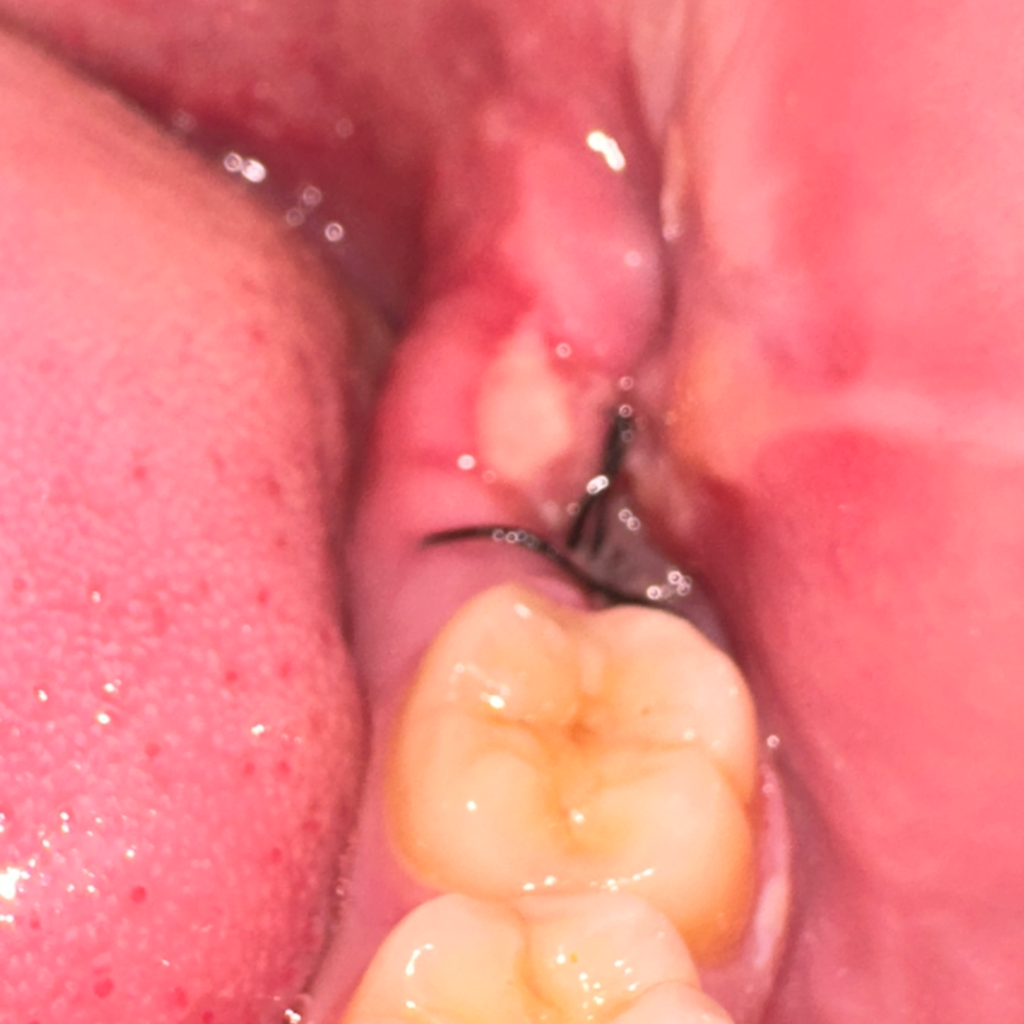

사랑니 발치 후 4일차 환부가 이상한데 괜탆은 건가요?

왼쪽 아래 사랑니 발치후 환부 모습이 좀 불안한데 병원에서는 자연스러운 낫는 과정이라고 합니다.

통증은 발치 당일에 비해 80% 수준 인 것 같고 정상적인 회복과정이 맞는 지 궁금하여 질문드립니다.

통증이 줄어들고 있으니 정상적으로 아물고 있는 것으로 보면 됩니다. 사진상에서도 잇몸이 부은 것도 안 보이고 하니 잘 아물고 있습니다.

크게 문제가 있어 보이진 않습니다. 발치한곳으로 음식물이 잘들어갈수 있으니 식사를 하시고 물로 여러번 헹구시는게 좋습니다.

특별히 이상이 보이지는 않습니다. 발치 후 극심한 통증이나 악취가 심하지 않으면 보통 괜찮습니다.